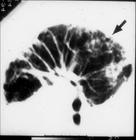

肺間質病的病理改變主要發生在肺泡間隔和鄰近的肺泡中。間質性肺疾病最早的表現為肺泡炎。開始因炎性細胞浸潤,肺泡壁增厚,肺泡腔縮小、閉鎖 型肺泡上皮損傷、消失 型細胞增生。毛細血管內皮細胞也壞變、消失。間質中成纖維細胞增生,膠原積聚,間質纖維變性。顯微鏡下觀察可見到間質水腫、增厚、逐漸纖維化。病情進展,上皮基礎膜破潰,間質成分由此突入肺泡腔,於是正常肺組織結構被破壞,代以纖維化組織,間以殘餘的擴大的肺泡和細支氣管。這是終末期的 ILD肺部表現.即蜂窩肺。

臨床表現 進行性加重的呼吸困難是較為突出的臨床症狀。伴有咳嗽,痰量少或為刺激性乾咳。呼吸道症狀無季節性緩解,常用的祛痰止咳藥物或抗生素效果差,病情多呈緩慢加重。體檢可見呼吸淺速,雙肺部可聽到高音調的細濕 音。重症者可見紫紺。部分患者(如IPF患者)中可見到杵狀指(趾)。胸部 X射線片可見雙肺瀰漫性網狀結節狀陰影。常規肺功能檢查可提供限制性通氣功能障礙和彌散功能降低的證據。